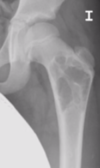

Fractura subcapital desplazada en paciente menor de 65 años

A

Reducción cerrada y osteosíntesis con tornillos canulados

Si 65-75: prótesis total

>75 a: prótesis parcial